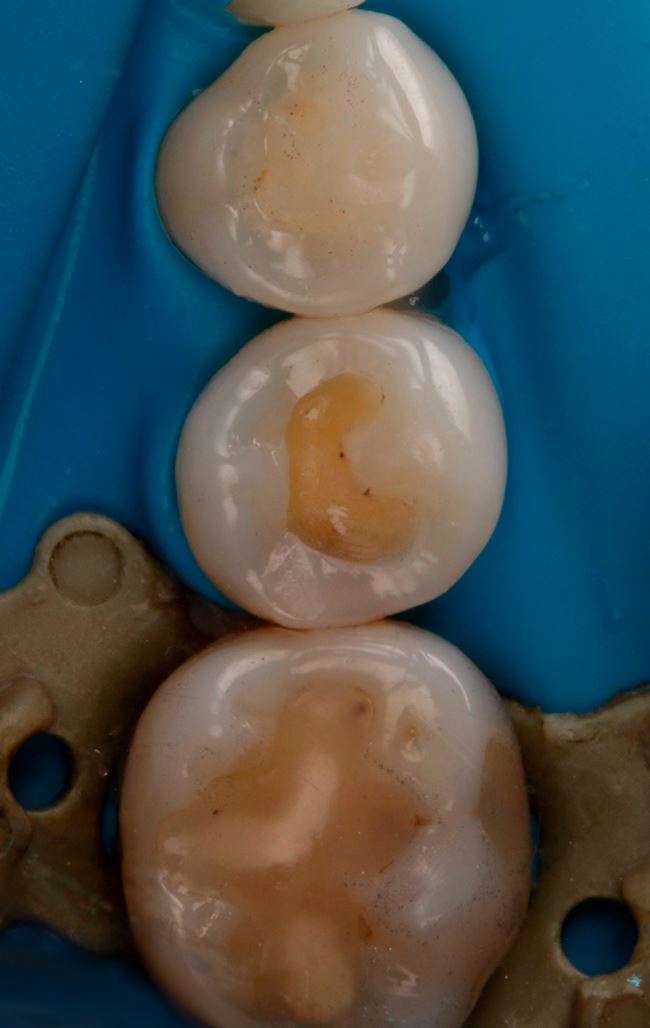

Przechodzimy jednak do zęba 45. Zdjęcie rentgenowskie (ryc. 2) nie daje jednoznacznej odpowiedzi na odwieczne pytanie nurtujące lekarzy dentystów: preparować czy nie? Jednak obraz z kamery DIAGNOcam zupełnie zmienia sytuację (ryc. 6).

Ryc. 6. Obraz z kamery DIAGNOcam. Ząb 45.

Ubytek na powierzchni dystalnej okazuje się całkiem duży, obejmuje znaczną część zębiny. Teraz nie ma już wątpliwości, że bez wypełnienia się nie obejdzie, a więc podajemy znieczulenie, zakładamy koferdam (ryc. 7) i przystępujemy do opracowania. Po usunięciu amalgamatu w dystalnej części ubytku widać ciemniejszą zębinę (ryc. 8). Usuwamy dystalną listewkę szkliwa i już widać wyraźne odwapnienie (ryc. 9). Dalej jest tylko ciemniej i głębiej (ryc. 10 i 11).